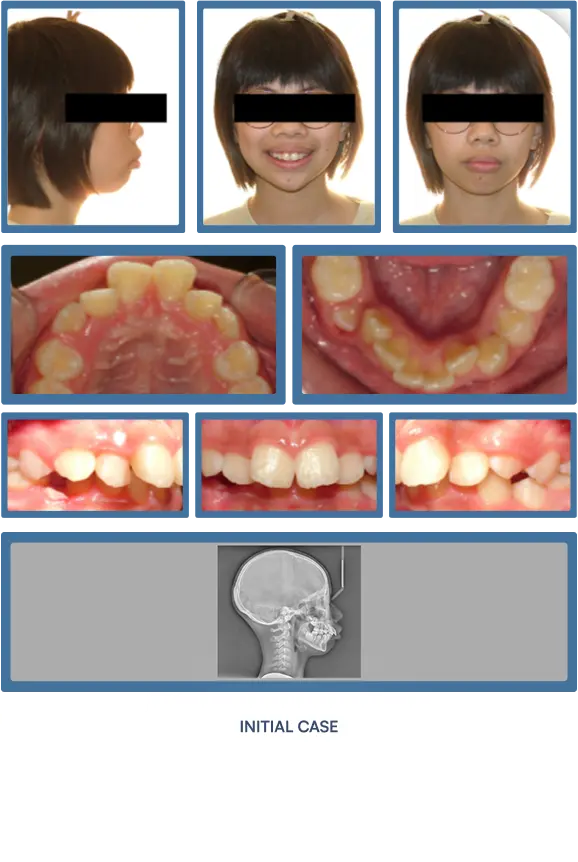

Orthodontic treatment does more than align teeth—it strategically improves the structural support of the lips and lower face. As teeth and jaws are brought into optimal alignment with braces or Invisalign®, many patients experience visibly fuller, more defined lips and an enhanced facial profile. These subtle yet impactful changes contribute to a more youthful, harmonious appearance—making orthodontics a powerful tool not only for oral health, but for facial aesthetics.